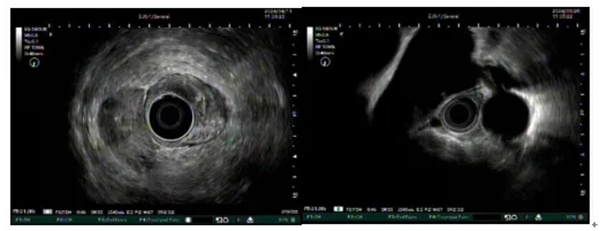

圖示超聲內(nei)鏡掃查直腸腫物(wù)及(ji)縱膈